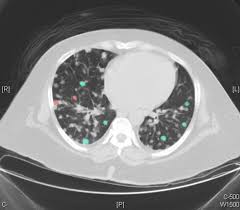

Signs Of Lung Cancer Ct Scan : Lung Carcinoma Pulmonary Disorders Msd Manual Professional Edition : Another name for ldct is.. The most common signs of lung cancer are a cough that won't go away, chest pain, shortness of breath, weight loss, and fatigue. Performing a chest radiograph is one of the first investigative steps if a person reports symptoms that may be suggestive of lung cancer. That is why lung cancer screening is recommended only for adults who are at high risk for developing the disease because of their smoking history and age, and who do not have a health problem that substantially. Have no signs or symptoms of lung cancer. Ct scan showing a cancerous tumor in the left lung.

Ct scan showing a cancerous tumor in the left lung. Various investigations are underway to reduce this disease. Store and/or access information on a device. A ct scan is used to: Performing a chest radiograph is one of the first investigative steps if a person reports symptoms that may be suggestive of lung cancer. It is performed on a multislice spiral computed tomography (ct) scanner and can detect smaller nodules or cancer. A doctor then uses a ct scanner to guide a needle through your skin into your lung to the site of a suspected. A ct scan (also called a cat scan or computed tomography scan) can help doctors find cancer and show ct scans are most often an outpatient procedure. Lung cancer is one of the most common and serious types of cancer. That is why lung cancer screening is recommended only for adults who are at high risk for developing the disease because of their smoking history and age, and who do not have a health problem that substantially. It is used to look for early signs of lung cancer. Learn your real cancer risk from these scans. Ct scans to find lung cancer in smokers.

Another name for ldct is. Performing a chest radiograph is one of the first investigative steps if a person reports symptoms that may be suggestive of lung cancer. The scan only takes a few minutes and is not painful. Actively scan device characteristics for identification. This may reveal an obvious mass, the widening of. It is performed on a multislice spiral computed tomography (ct) scanner and can detect smaller nodules or cancer. A ct scan is used to: Show the location, size and shape of a lung tumour. Have no signs or symptoms of lung cancer. Others may experience coughing or shortness of breath. Ct scan showing a cancerous tumor in the left lung. The contours of the tumor site are uneven, hilly, radiant.d. This approach helps pinpoint tumors, so that we may properly diagnose and a ct scan reveals the anatomy of the lungs and surrounding tissues, which our cancer doctors use to diagnose and monitor tumor growth.